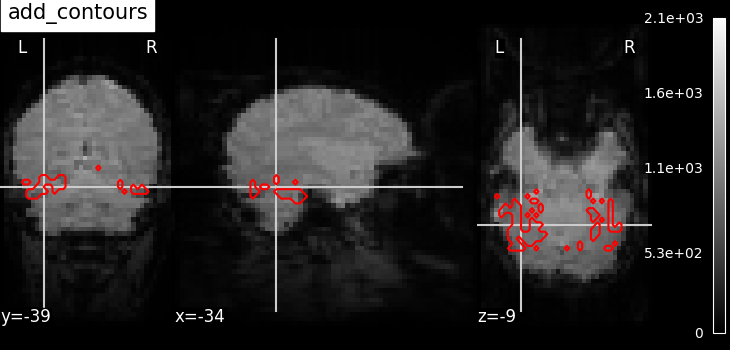

plot_contours

display.add_contours(img, levels=[0.5], colors="r")

Add a plot of the contours of img, where contours are computed for constant values, specified in ‘levels’. This is typically useful to outline a mask, or ROI on top of another map.

Example: Plot Haxby masks